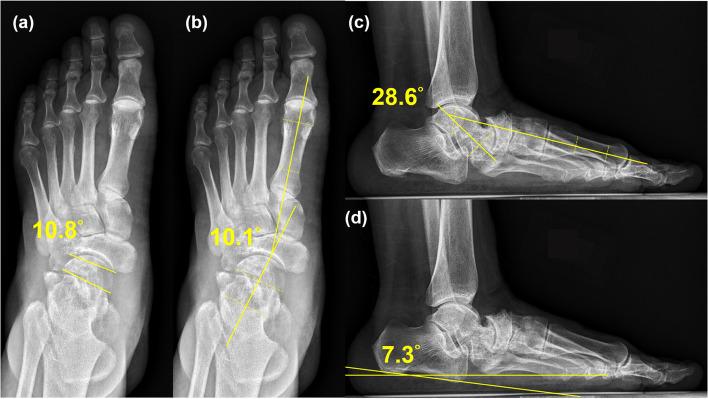

RESULTS

The used four radiographic parameters (Meary's angle in anteroposterior and lateral view, talonavicular coverage angle, calcaneal pitch) demonstrated significant differences (P < .05) preoperatively and postoperatively, but those between the postoperative values and the values at the last follow-up session did not, indicating that strut allograft was able to maintain normal alignment. The mean American Orthopaedic Foot & Ankle Society Ankle-Hindfoot scores at 2 years postoperatively revealed significant improvement from baseline, from 60.2 to 84.2 (P < .05). The 12-item Short Form Health Survey scores also improved significantly (P < .05). All patients reported substantial pain relief and exhibited improved functional outcomes and gait patterns.

使用的 4 项影像学参数(前后位和侧位的 Meary 角、距舟覆盖角、跟骨倾斜角)在术前和术后均有显著差异(P<.05),但术后值与末次随访时的差异无统计学意义,表明支撑同种异体骨能够维持正常的对线。术后 2 年的美国矫形足踝协会踝关节-后足评分平均从基线的 60.2 分显著提高到 84.2 分(P<.05)。12 项简明健康调查问卷评分也有显著改善(P<.05)。所有患者均报告疼痛明显缓解,并表现出功能改善和步态模式的改善。